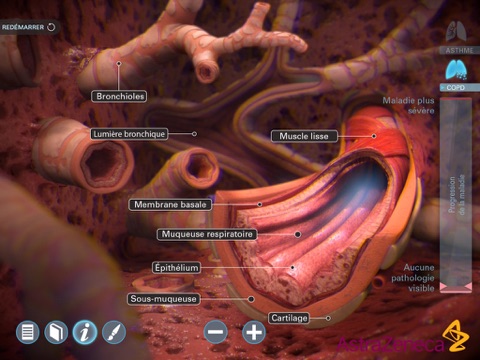

Living Lung est une application développée par AstraZenecaet destinée aux médecins. Elle présente en 3D lapparence des poumons des malades atteints dasthme ou de Broncho-Pneumopathie Chronique Obstructive (BPCO) en fonction de lévolution de la maladie.

Cette application, qui contient également des légendes anatomiques et un outil de dessin, est un support pour expliquer aux patients leur maladie.